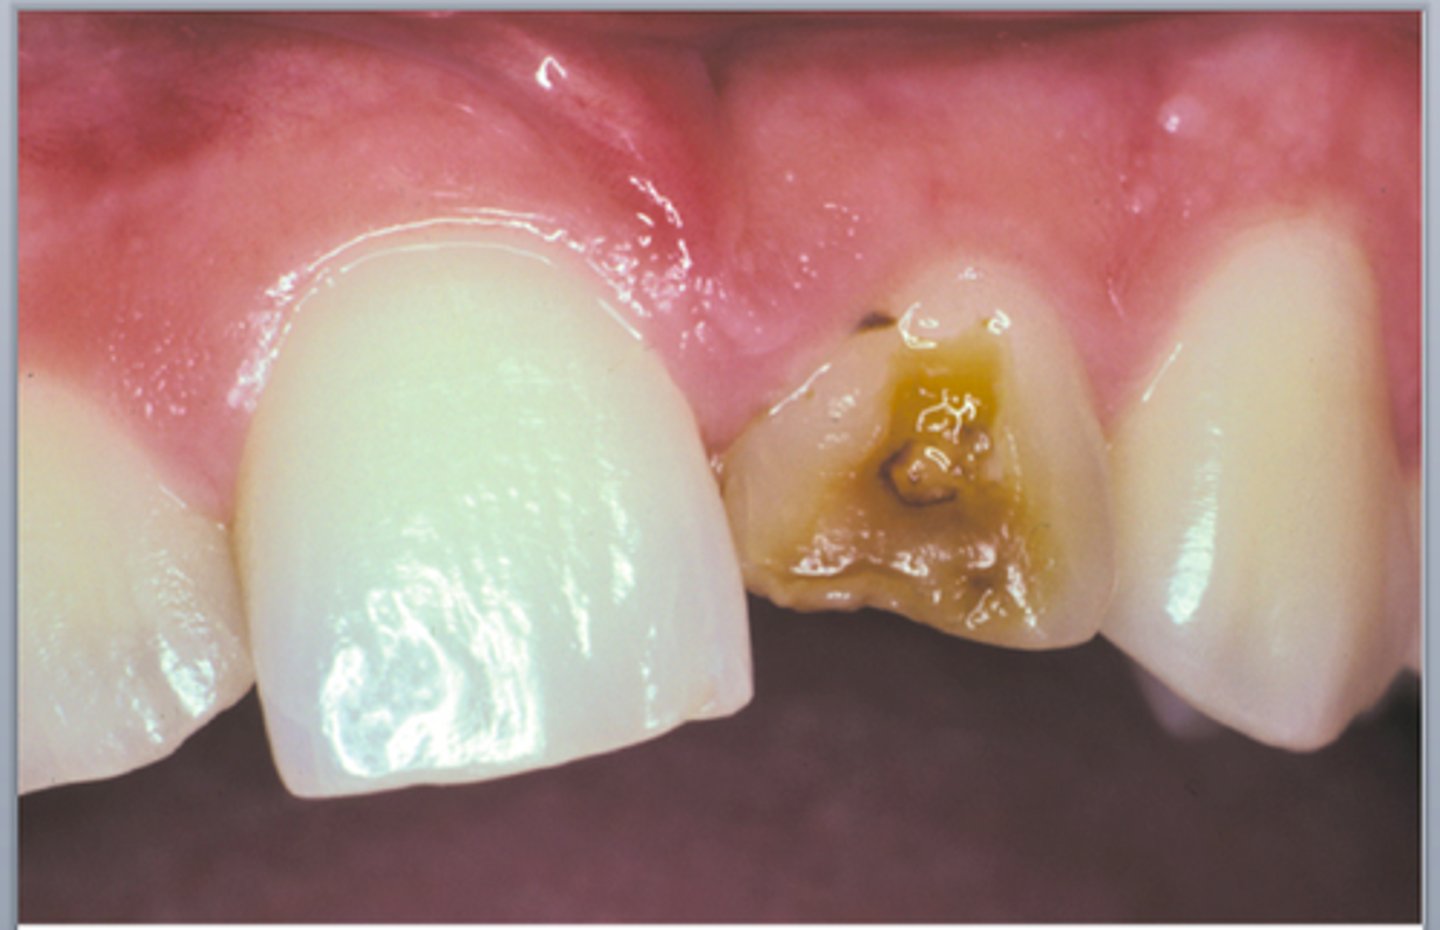

Broken coronal portion of a canine. What do you do?

Conservative endo and prepare post and core.